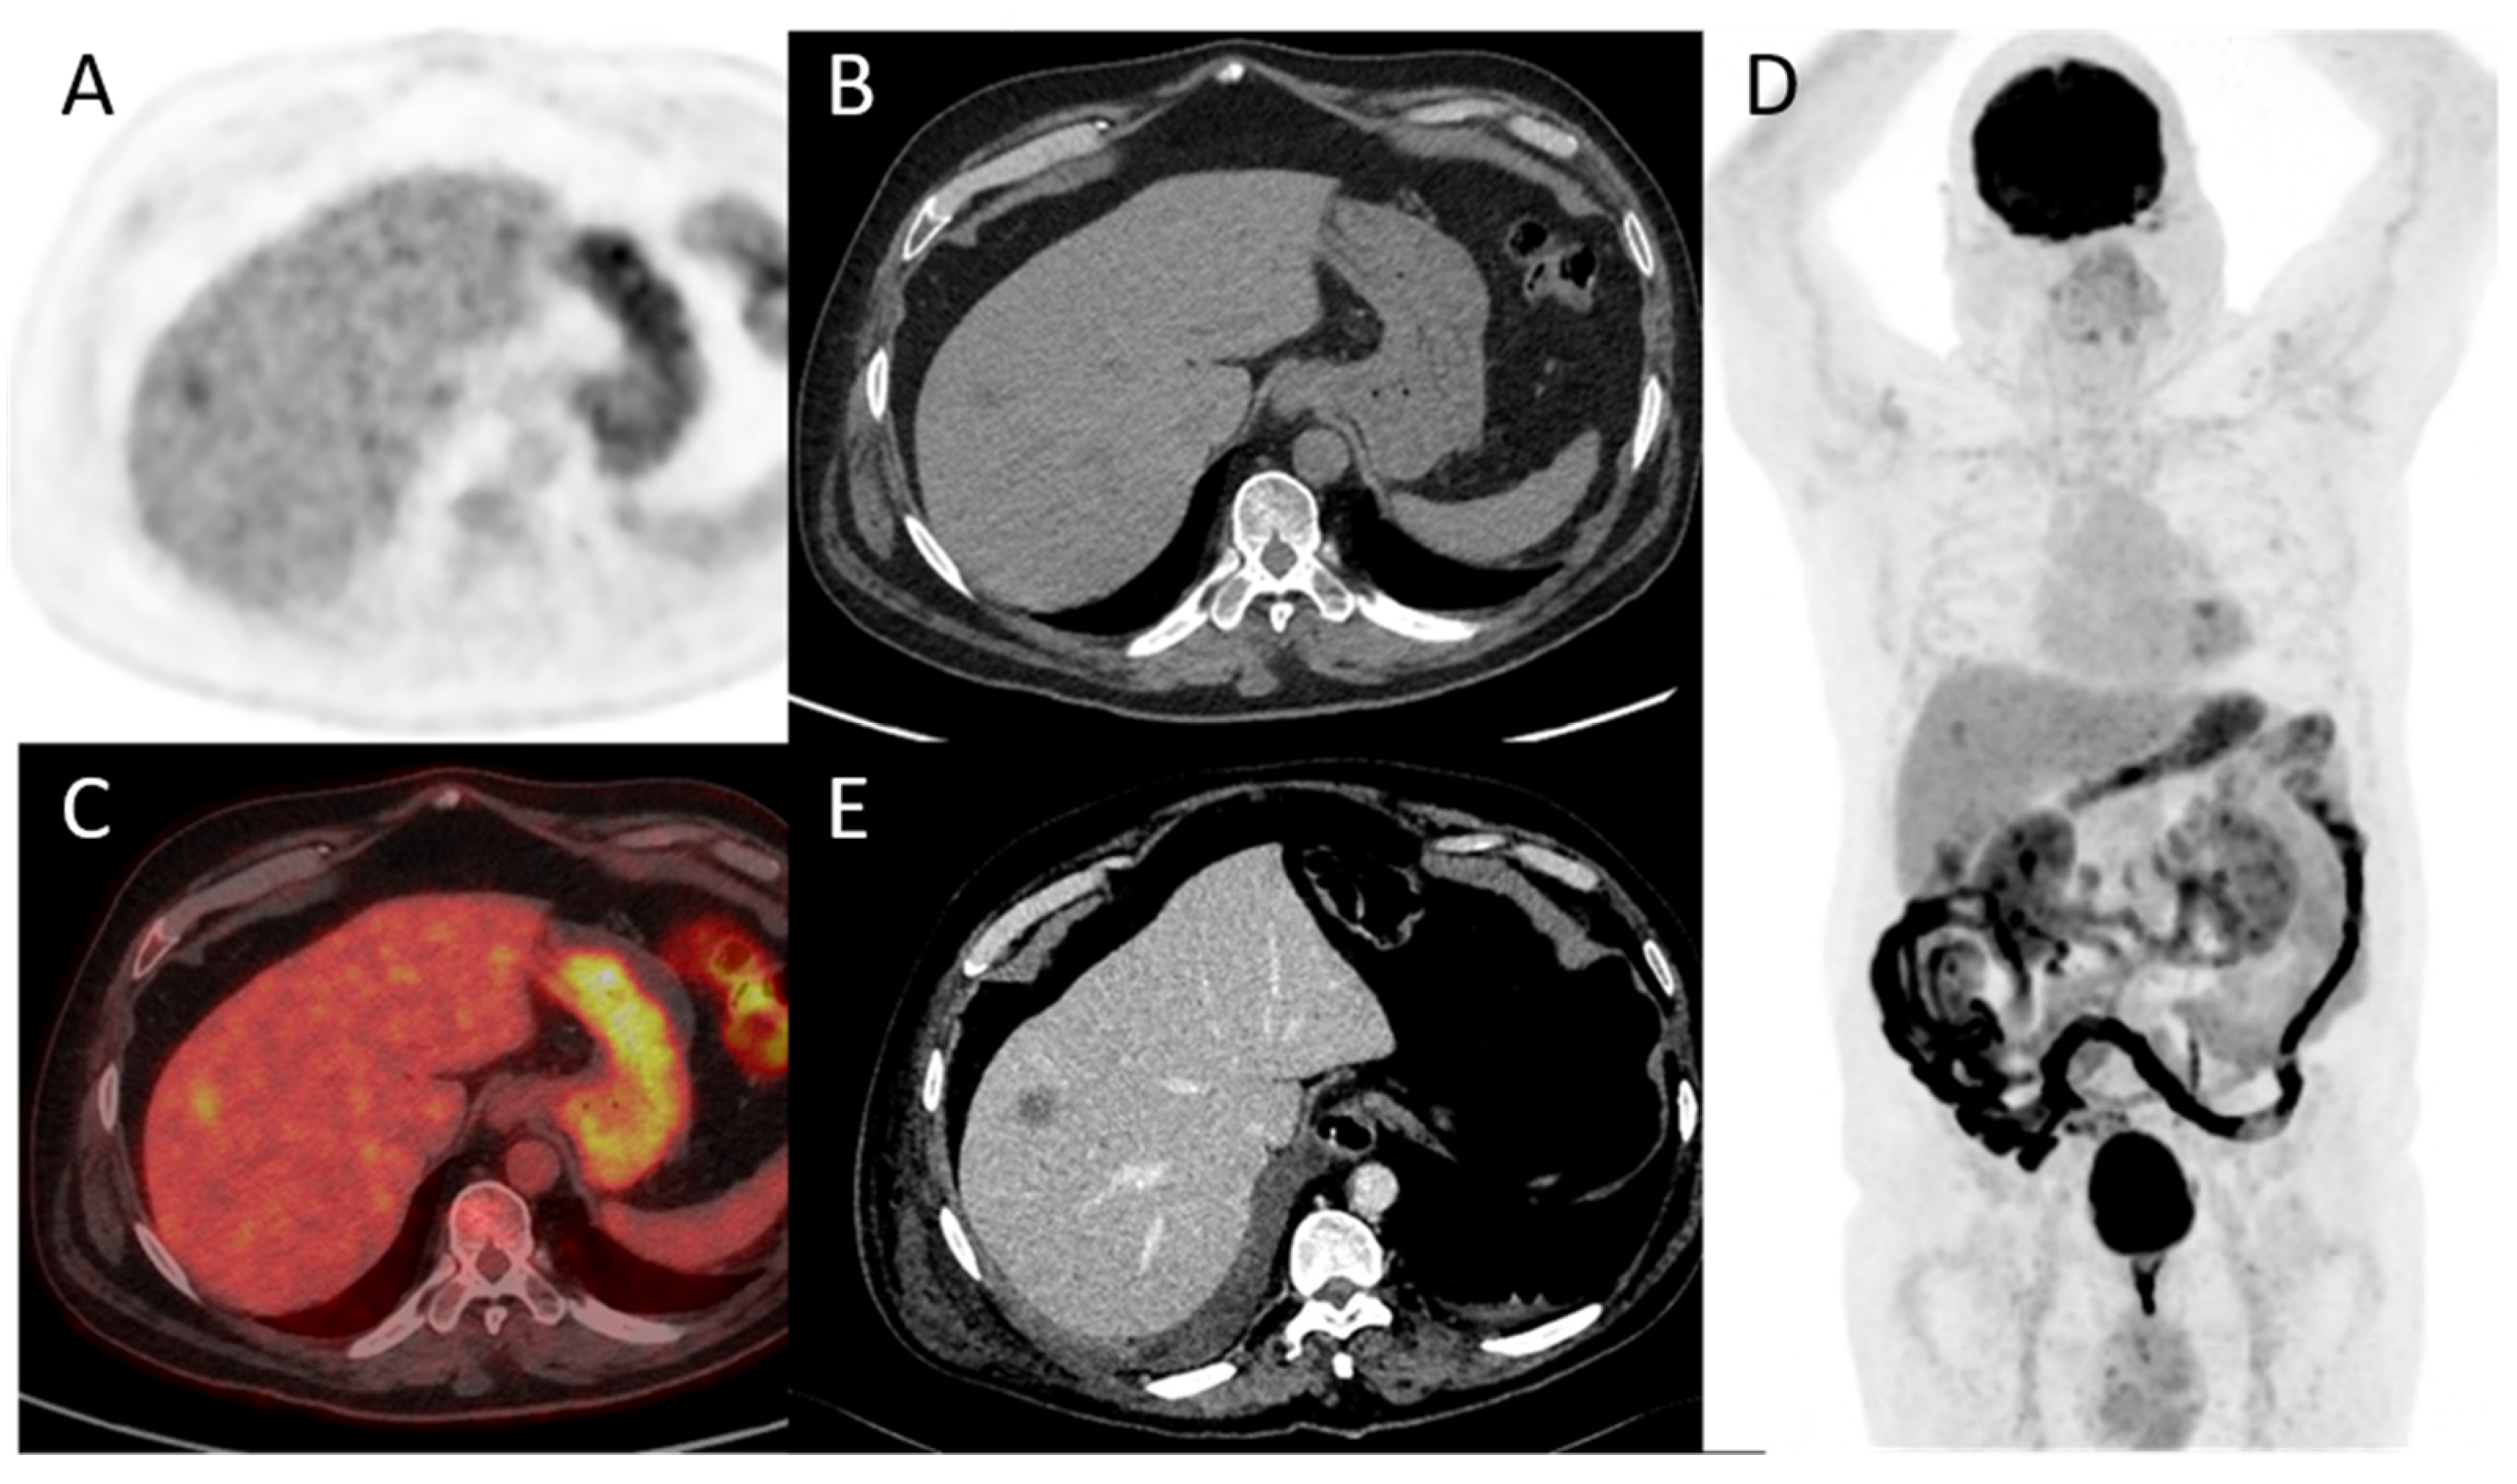

- Kollberg, P.; Almquist, H.; Bläckberg, M.; Cwikiel, M.; Gudjonsson, S.; Lyttkens, K.; Patschan, O.; Liedberg, F. [18F]Fluorodeoxyglucose-positron emission tomography/computed tomography response evaluation can predict histological response at surgery after induction chemotherapy for oligometastatic bladder cancer. Scand. J. Urol. 2017, 51, 308–313. [Google Scholar] [CrossRef]

- Abrahamsson, J.; Kollberg, P.; Almquist, H.; Bläckberg, M.; Brändstedt, J.; Lyttkens, K.; Simoulis, A.; Sjödahl, G.; Sörenby, A.; Trägårdh, E.; et al. Complete metabolic response with [ 18 F]fluorodeoxyglucose-positron emission tomography/computed tomography predicts survival following induction chemotherapy and radical cystectomy in clinically lymph node positive bladder cancer. BJU Int. 2021, 129, 174–181. [Google Scholar] [CrossRef]